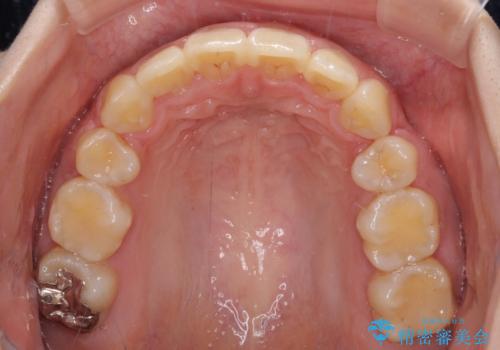

- クリアブラケット

- 上下前歯を部分矯正したところ出っ歯になってしまったとのことで来院された患者様です。

上下左右第一小臼歯4本を抜歯して、積極的に口元を引っ込めるよう、ワイヤー装置にて矯正治療を行うこととしました。

治療後には口が閉じやすくなり、患者様には大変満足していただきました。